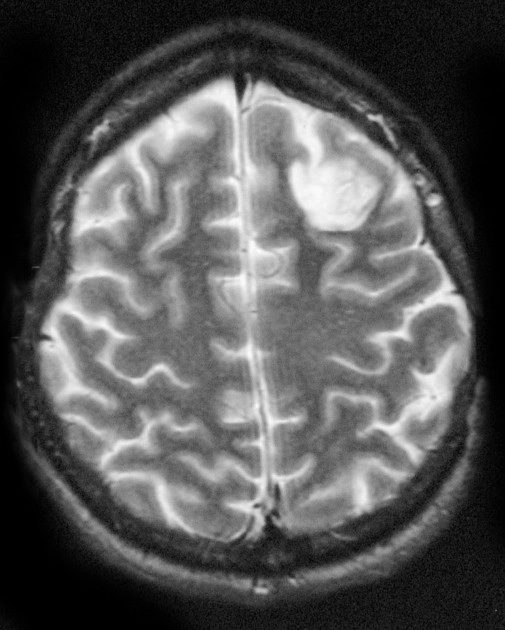

Di căn nhu mô não (Parenchymal metastases)